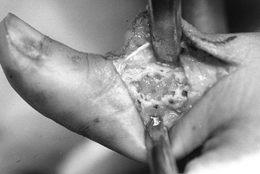

juxtacortical, expanding zone of radiolucency at the

epiphyseometaphyseal end of a long bone (Fig. 127.3A, Fig. 127.3B).

The tumor is a well-delineated lesion with irregular endosteal margins.

There is usually no reactive host bone at the periphery of the lesion.

According to the staging system for benign bone tumors, the lesion most

typically presents as an active (stage 2) or aggressive (stage 3)

tumor. The tumor frequently extends to the subchondral bone of the

articular surface and destroys the surrounding cortex, extending into

the soft tissue. Because of the rapid expansion, a periosteal reaction

is seldom seen. The combination of substantial destruction and poor

margination may suggest malignancy.

![]() |

|

Figure 127.3. AP radiograph (A)

of a giant cell tumor (GCT) of bone shows a radiolucent lesion of the lateral distal femur involving the epiphysis and the metaphysis. It has destroyed the cortex although the periosteum is intact, and it is well delineated although not well marginated. In the lateral film (B), it is apparent that the lesion extends down to the subchondral bone distally and along the patellofemoral joint. This has the typical appearance of a GCT of bone. AP (C) and lateral (D) radiographs show the postoperative findings in this patient who was treated with extensive curettage, burring of the cavity, and packing with PMMA bone cement and reinforcing metal rods. |